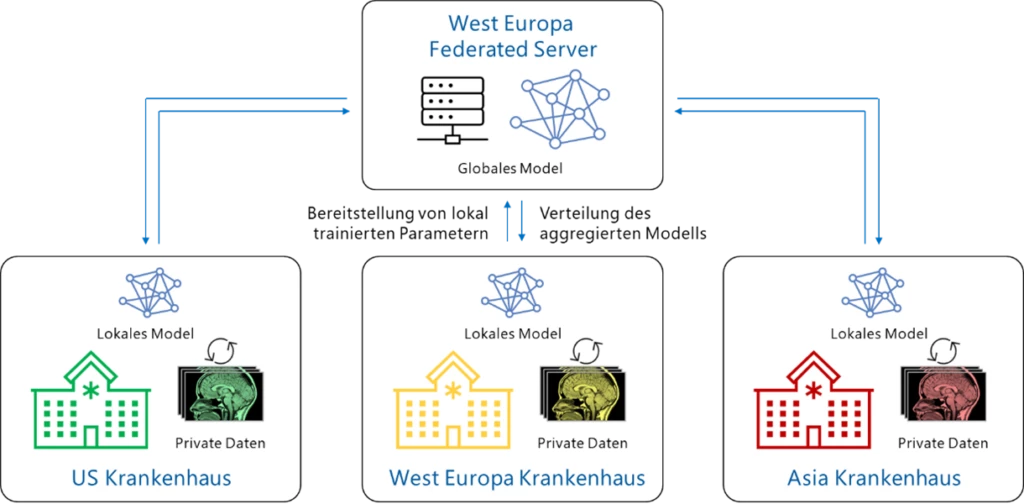

Beim Federated Learning können mehrere Akteure gemeinsam ein Machine-Learning-Modell trainieren, ohne dass dafür jedoch Daten ausgetauscht werden müssen.

Die folgende Abbildung illustriert die Vorgehensweise:

Das Hauptmerkmal von Federated Learning ist, dass die lokalen Daten der Teilnehmenden niemals weitergegeben werden. Jeder Akteur erhält regelmäßig eine Kopie des globalen Modells und führt ein lokales Training mit lokalen Daten durch. Die einzigen Informationen, die ausgetauscht werden, sind die aus dem Training gewonnenen „Erkenntnisse“, die sogenannten Aktualisierungen der Modellparameter.

Über den Server werden die Werte aller teilnehmenden Akteure zu einer neuen Modellversion zusammengefasst, und das aktualisierte Modell wird dann wieder an die Akteure verteilt, um die nächste kollaborative Trainingsrunde einzuleiten. Dieser Prozess wird so lange wiederholt, bis ein zufriedenstellendes Modell vorliegt, und kann ebenso für ein kontinuierliches Training genutzt werden, um das Modell durch neue Datenpunkte anzureichern und zu verfeinern.